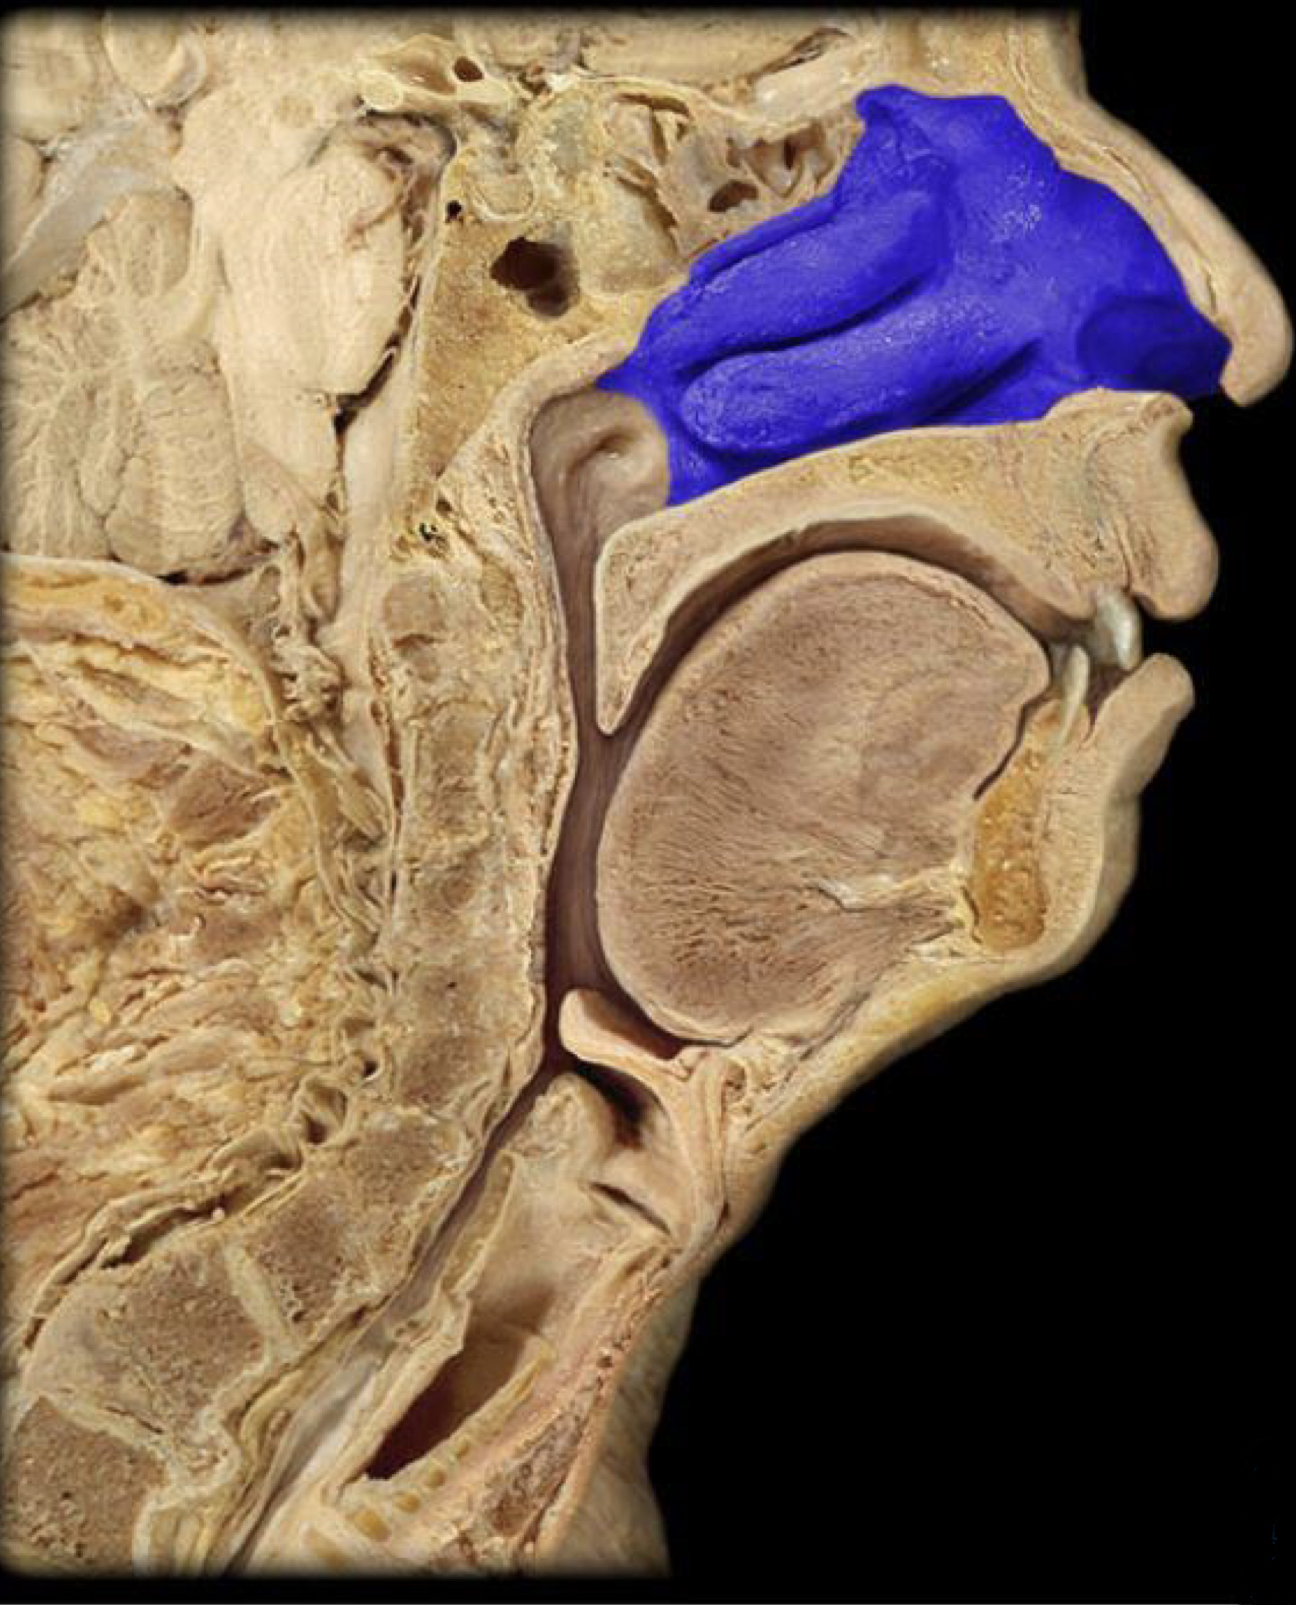

What structure is highlighted in blue?

Nasopharynx